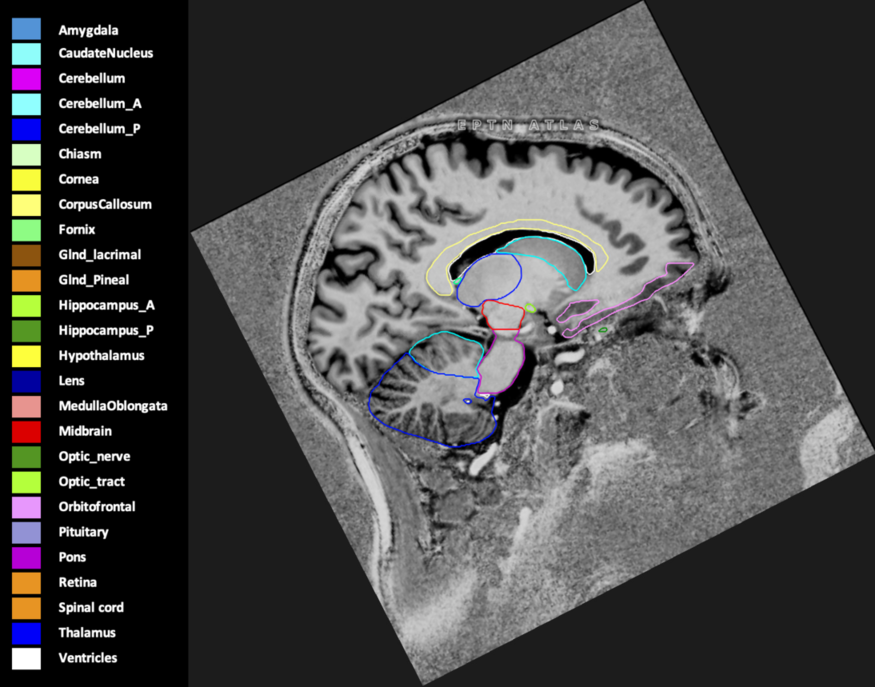

Eekers et al. have published an international neurological atlas for contouring of organs at risk in consensus with the European Particle Therapy Network (EPTN) in 2018 and an update in 2021. The purpose of this consensus atlas is to decrease inter- and intra-observer variability in delineating OARs relevant for neuro-oncology.

Included are all OARs known to be relevant for radiation-induced toxicity in neuro-oncology: brain, brainstem (midbrain, pons, medulla oblongata), chiasm, cerebellum (anterior & posterior), cochlea, cornea, hippocampus (anterior & posterior), hypothalamus, lens, lacrimal gland, optic nerve, pituitary, skin, and vestibular & semicircular canals. To further facilitate research on cognition, vision and radiological changes after irradiation of the brain, potential clinically-relevant OARs are included: amygdala, caudate nucleus, cerebellum (anterior & posterior), corpus callosum, fornix, macula, optic tract, orbitofrontal cortex, periventricular space (PVS), pineal gland, and thalamus.

Three-dimensional delineation of the 25 consensus OARs for neuro-oncology are shown on CT (WW/WL 120/40, 3000/600), 3T MR images, (T1Gd, T2FLAIR 1mm) and 7T MR (MP2RAGE 0.7 mm). All are presented in transversal, sagittal and coronal view.